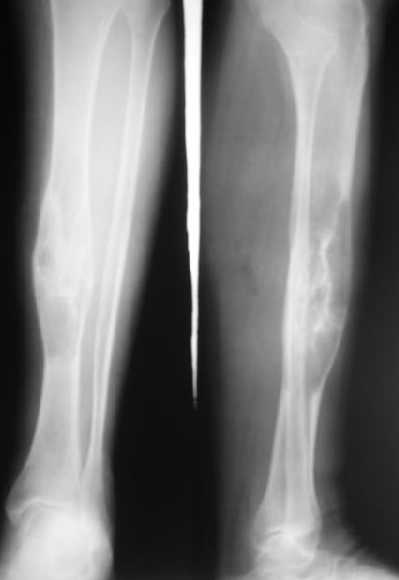

Пациентке дважды делали биопсию, второй раз - довольно расширенную,

через доступ 5 см. Стекла смотрели в онкодиспансере и у нас,

морфологи единодушно поставили гигантоклеточную опухоль. Диафизарная

локализация для которой очень нехарактерна, 1-2%.

Исходя из диагноза, выглядела адекватной сегментарная резекция,

которая дает наименьшее количество рецидивов.

Напомню, пациентке 61 год, она еще практически слепая, т.е.

функциональные потребности невысокие.